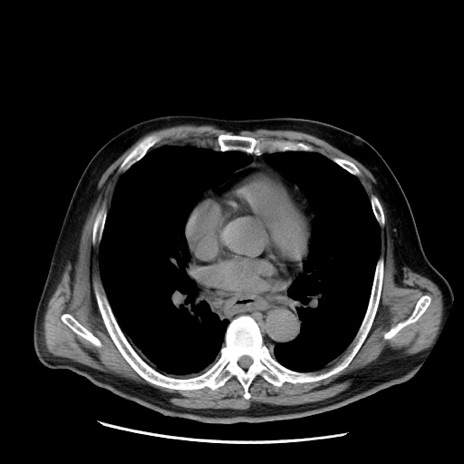

症例20(横断像)

【症例】 60歳代男性

【主訴】 腹部膨満、嘔吐

【現病歴】5日前頃より倦怠感を認め食事量減少し4日前の朝嘔吐、食事摂取困難となった。 3日前近医受診し点滴施行され整腸剤などを処方された。 当日他院を受診し、腹部膨満著明、炎症反応の上昇(CRP10.8、WBC11200)あり、紹介受診となる。

【身体所見】 意識JCS1 受け答えがはっきりしないBP 111/57mHg、 P 67bpm、、BT35.2°C、SpO2 97%(RA)、 腹部:膨隆、打診で鼓音あり、全体的に圧痛有り、腸蠕動音(-)、反跳痛ははっきりせず。

【データ】WBC 11400、CRP 14.20